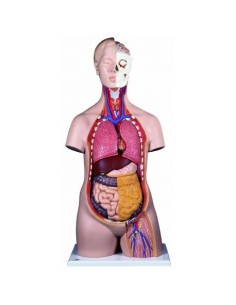

Scopri il Mondo dell’Anatomia con Modelli anatomici di Precisione

Modelli Anatomici Dettagliati per Ogni Necessità

Dal cranio in 22 parti con incastri magnetici ai modelli di colonna vertebrale, da quelli di articolazioni a quelli di cuore, ogni pezzo della nostra collezione è progettato per un’immersione totale nello studio dell’anatomia umana. I nostri modelli, realizzati tramite scansioni di ossa vere, garantiscono un’esperienza tattile autentica e una fedeltà di peso quasi identica agli originali.

Strumenti Didattici Innovativi per l’Educazione e la Pratica Medica

Essenziali per studenti e professionisti, i nostri modelli anatomici sono strumenti didattici che permettono di osservare le strutture anatomiche con precisione, eliminando la necessità di dissezioni o studi invasivi. Sono inoltre utili per spiegare ai pazienti le patologie, rendendo la comunicazione più efficace e risparmiando tempo prezioso.